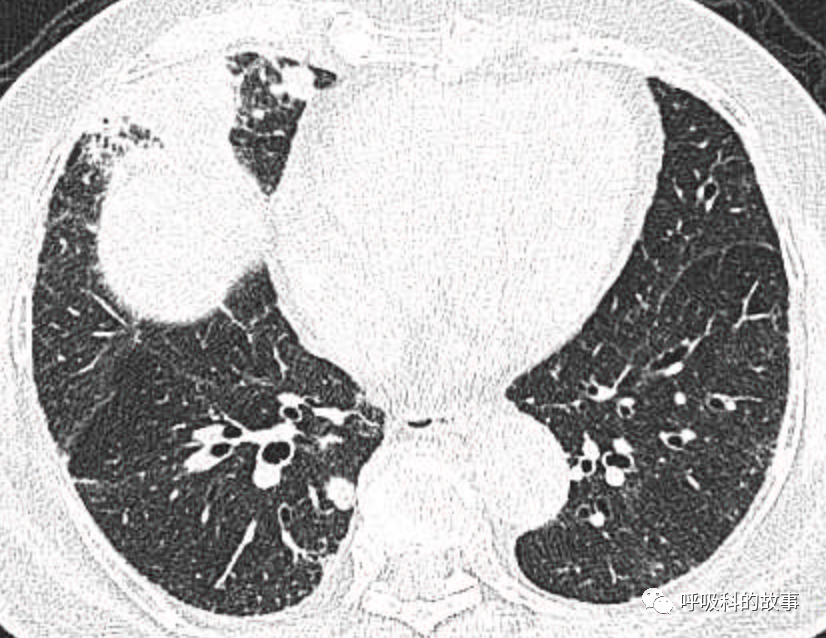

可是就在今年初,患者曾住在某院某科室,因为其他内科疾病住院。当时肺部CT也发现了在右中叶内侧段的高密度实变影,由于影像很类似肺炎,因此当成肺炎治疗。

图12-14:该患者各个角度的影像图像

(上下滑动查看全部图片)